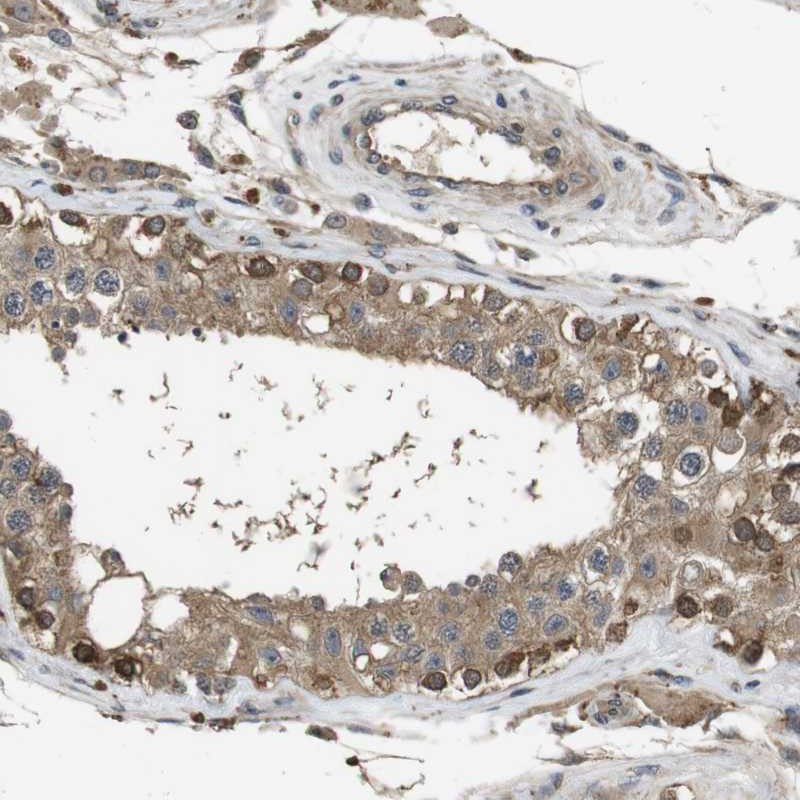

Immunohistochemical staining of human testis shows strong cytoplasmic positivity in a subset of cells in seminiferus ducts.